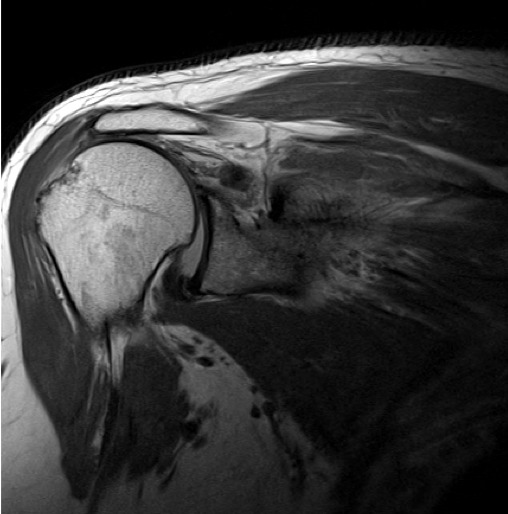

← Reverse Shoulder Replacement

By Sujit Jos | Published February 10, 2024 | Full size is 508 × 514 pixels shoulder-power-after-reverse-shoulder-Dr-Sujit-Jos Fatty-infiltration-rotator-cuff Bookmark the permalink.JOINT CLINIC